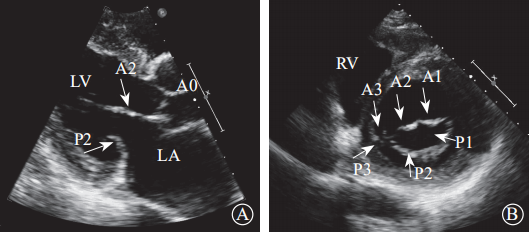

通过采集以下切面显示二尖瓣瓣叶各扇叶。(1)胸骨旁左心室长轴切面,显示A2、P2(图5A);(2)二尖瓣水平短轴切面,显示整个前后叶(图5B);(3)心尖四腔心切面,显示A2、P2(图6A);(4)心尖长轴切面,显示A2、P2(图6B);(5)心尖二腔心切面,显示A1、P3(图7A);(6)心尖二尖瓣交界处长轴切面,显示P1、A2、P3(图7B)。经胸超声心动图通过上述切面评价MR的机制、程度以及部位,并确定瓣膜运动异常的扇叶。

图 5 经胸二维超声心动图显示二尖瓣瓣叶各扇叶 A. 胸骨旁长轴切面,显示二尖瓣前叶 A2 处、二尖瓣后叶 P2 处;B.二尖瓣水平短轴切面,显示二尖瓣前叶 A1、A2、A3 及二尖瓣后叶 P1、P2、P3